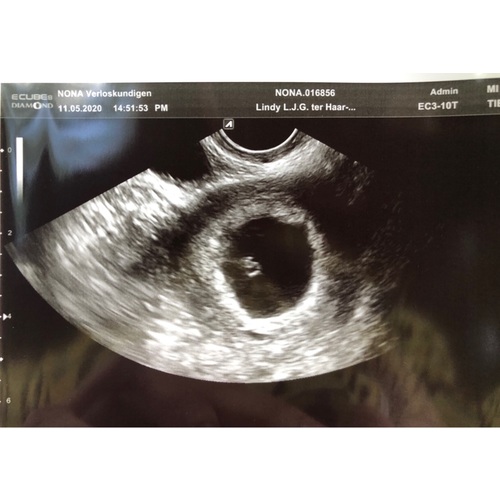

Dit was mijn echo 5+5 ( er staat geloof ik ander termijn op , ik was echt veel terug gezet, door een gemiste menstruatie die dus eigenlijk gewoon gemist was en geen zwangerschap was )

Ze twijfelden wel of het goed zat, want groeide eerst ook niet lekker, met 7 weken terug gegaan voor een echo en het was gewoon gegroeid en zit prima ! Onderhand 30+4 van ons mannetje !